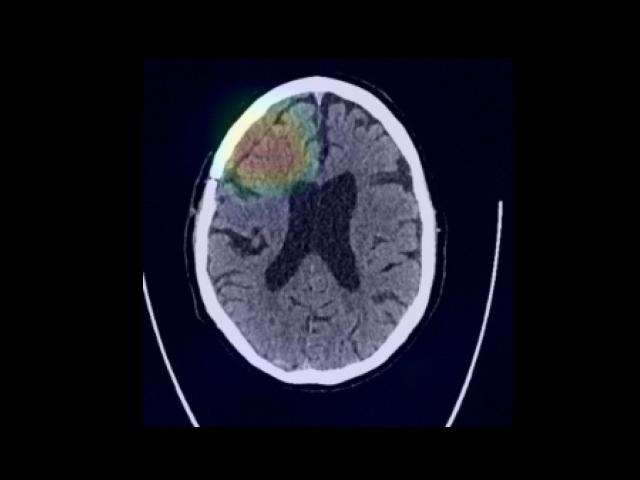

Sample Gallery